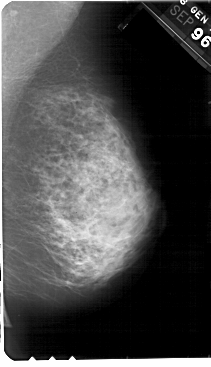

A_1531_1.RIGHT_MLO

RIGHT_MLO LINES 5491 PIXELS_PER_LINE 3151 BITS_PER_PIXEL 12 RESOLUTION 43.5 NON_OVERLAY

FILE: A_1531_1.LEFT_CC.OVERLAY

TOTAL_ABNORMALITIES 1

ABNORMALITY 1

LESION_TYPE CALCIFICATION TYPE PLEOMORPHIC DISTRIBUTION CLUSTERED

ASSESSMENT 4

SUBTLETY 4

PATHOLOGY MALIGNANT

TOTAL_OUTLINES 1

BOUNDARY